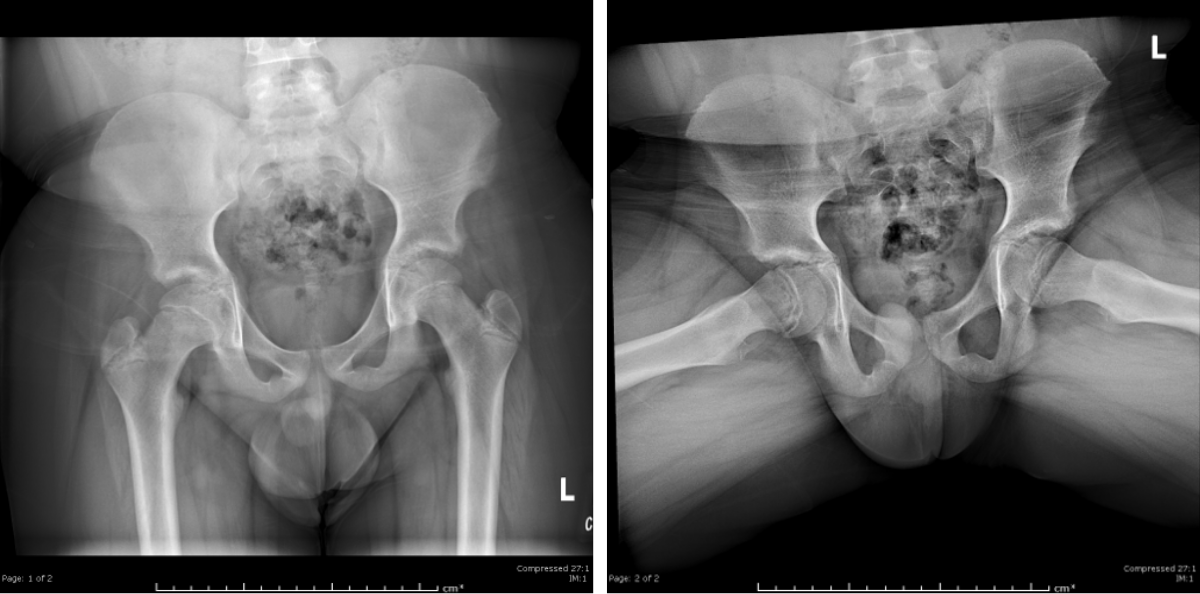

Slipped Capital Femoral Epiphysis

Note the medial and posterior displacement of the right femoral head and widened physis. Frog lateral views are generally more sensitive.